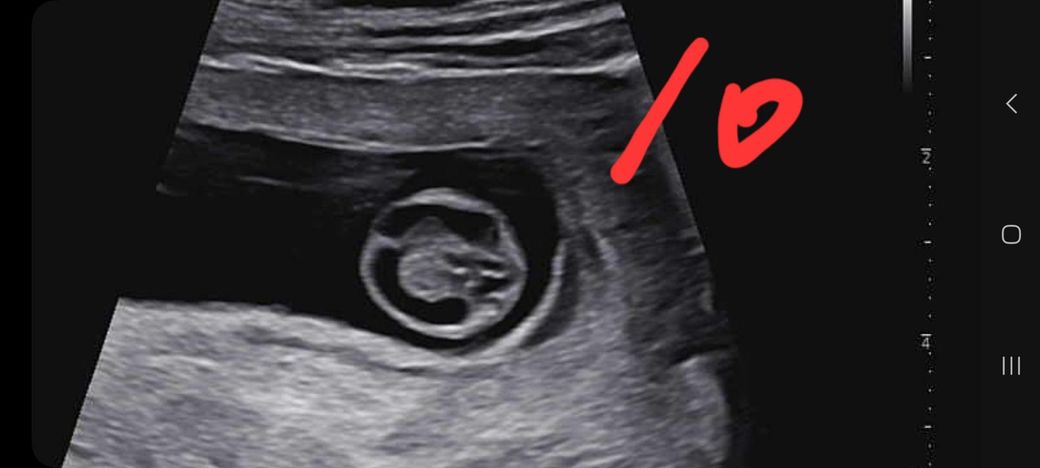

임신 12주차 태아 뇌 초음파 좀 봐주세요ㅜ

임신 12주차 이며 10주차 때 뇌 모양이 신경쓰인다고

12주차 초음파 때 다시 보자 하시더라구요

그래서 오늘 다녀왔는데

앞쪽(이마 쪽)이 신경 쓰인다며 소견서 써줄테니

대학병원 다녀와보라 하시네요ㅜ

사진 한번 보시구 이야기, 조언 좀 부탁드립니다.

(10주차 사진은 10이라 적었습니다.)

• 1번 째 사진